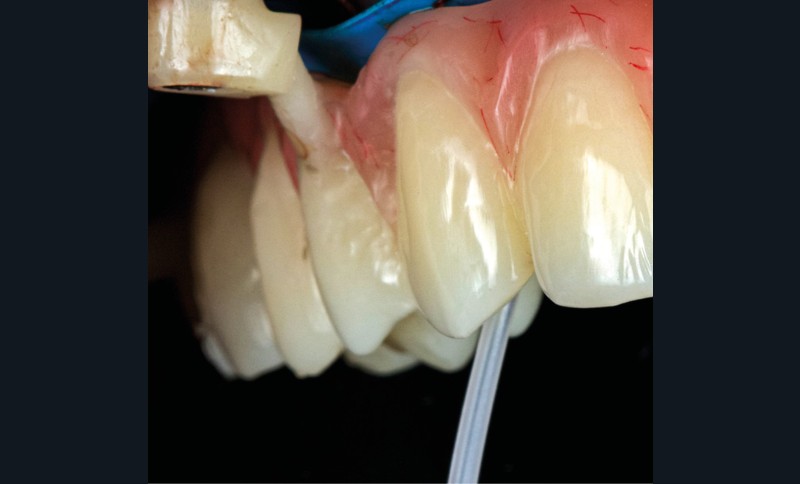

Après une extraction atraumatique des dents résiduelles, nous passons au 3e étage qui est le guide de forage stéréolithographique. La séquence de chirurgie Full guided est passée et les implants ont été torqués entre 40 et 50N.cm2 (fig. 6, 7, 8). Cette stabilité primaire dans les sites d’extraction et des sites greffés a permis la mise en charge immédiate du bridge complet provisoire. Des études cliniques [3, 4, 5] ont montré que la mise en charge immédiate dans les sinus greffés ne pose aucune contre-indication. Le 4e étage est donc celui du bridge provisoire transvissé à l’étage de base et solidarisé en bouche par l’intermédiaire de cylindres provisoires sur piliers MUA, avec une colle duale (GC-LinkForce). L’espace entre les implants et l’alvéole a été comblé par une xénogreffe (Bio-Oss Geistlich). Les profils d’émergence sont travaillés et parfaitement polis. Enfin, le bridge est mis en place, torqué à 20.cm2, équilibré et les consignes postopératoires ont été rappelées à la patiente (fig. 9 et 10).